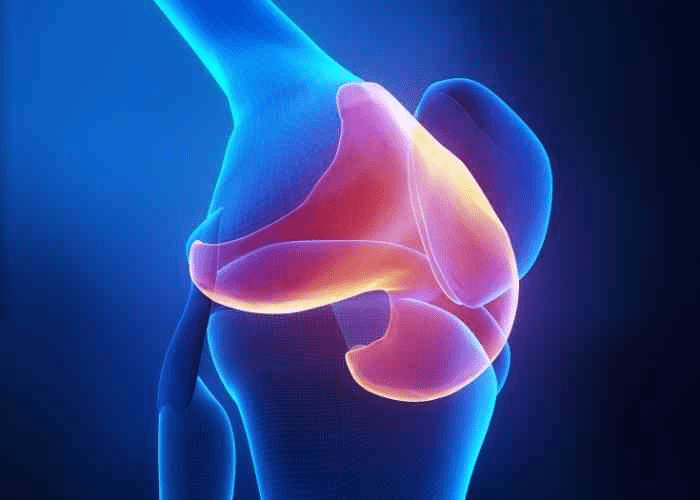

Knee pain affects millions, often sneaking up as we age. It starts with a twinge during walks, then escalates to constant discomfort.

Simple tasks like climbing stairs become daunting. Over time, this can limit your independence and joy in daily life.

But why does this happen? Cartilage wear and inflammation play key roles, leading to that nagging ache.

Benefit 9: Potential Anti-Inflammatory Support

Benefit 8: Easing Daily Aches

Benefit 7: Supporting Cartilage Health